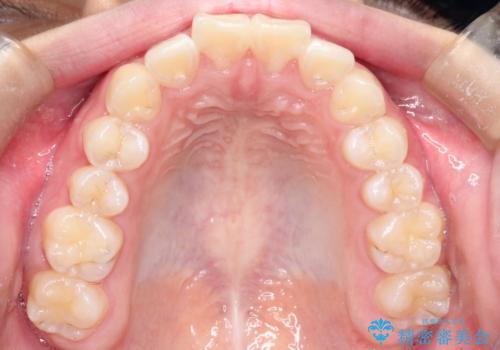

インビザラインによる出っ歯の非抜歯矯正

- 前歯が出ているのを主訴に来院されました。

上の前歯が前方に傾斜しており、上の前歯と下の前歯が接触していない状態でした。

上の奥歯を後方に移動させて、前歯を引っ込める計画としました。

しっかり使っていただけたので、スムーズに治療を終了することができました。